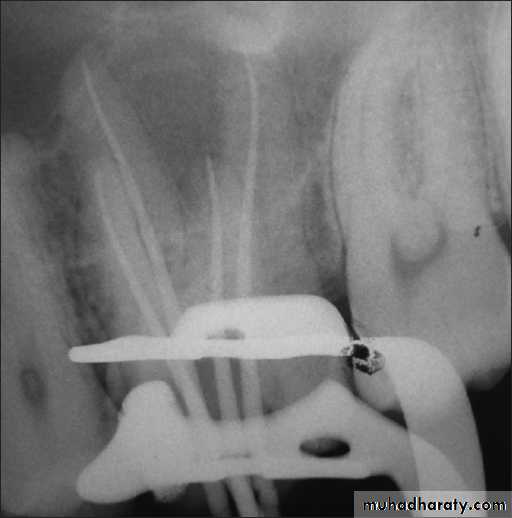

Recognition

• Removal of shortened file from the canal• Loss of original working length

• Radiograph is essential for confirmation